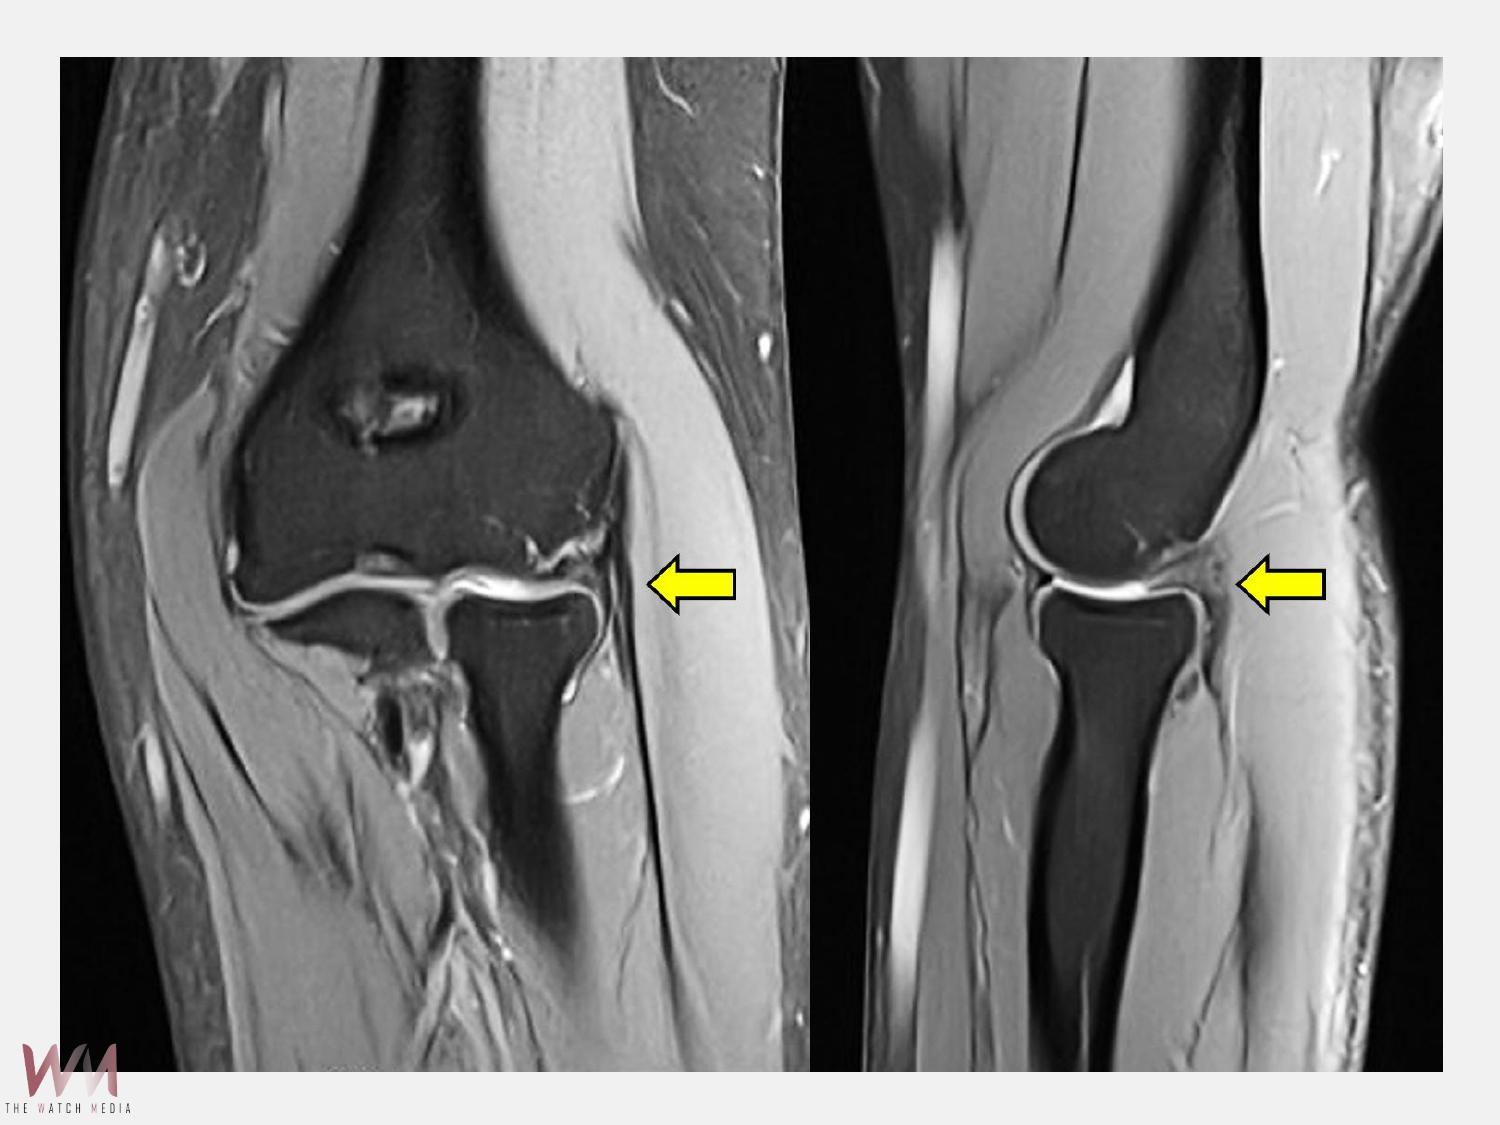

膜皺襞增生與軟骨軟化。這類結構性病因若僅以「網球肘」的治療方式處理,往往難以根治。

陳重宇醫師說,外側手肘疼痛並非全是「網球肘」,其他常見原因包括:韌帶或關節囊損傷、剝離性軟骨炎、骨刺或退化性關節炎、滑膜皺襞症候群(synovial plica syndrome)和神經壓迫性疼痛。針對手肘的結構性病因,微創關節鏡手術是一個安全且效果良好的選擇。以C小姐為例,手術透過關節鏡直接觀察肘關節內部結構,精準鬆解發炎的肌腱附著點,並清除增生的滑膜皺襞。手術僅需數個約1公分的小切口,創傷小、出血少,術後疼痛明顯減輕,復原速度快。